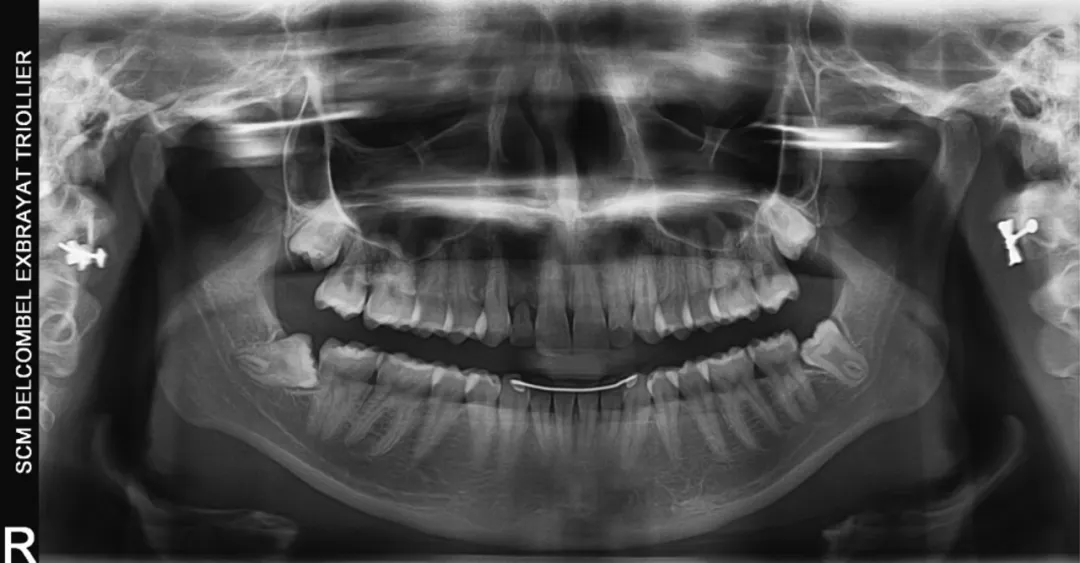

3 号病例 - Patrick EXBRAYAT 医生(图 36 至 49)

女性患者,侧切牙 12 发育不全,长期使用临时修复手段。

图 36 :术前全景 X 线影像。